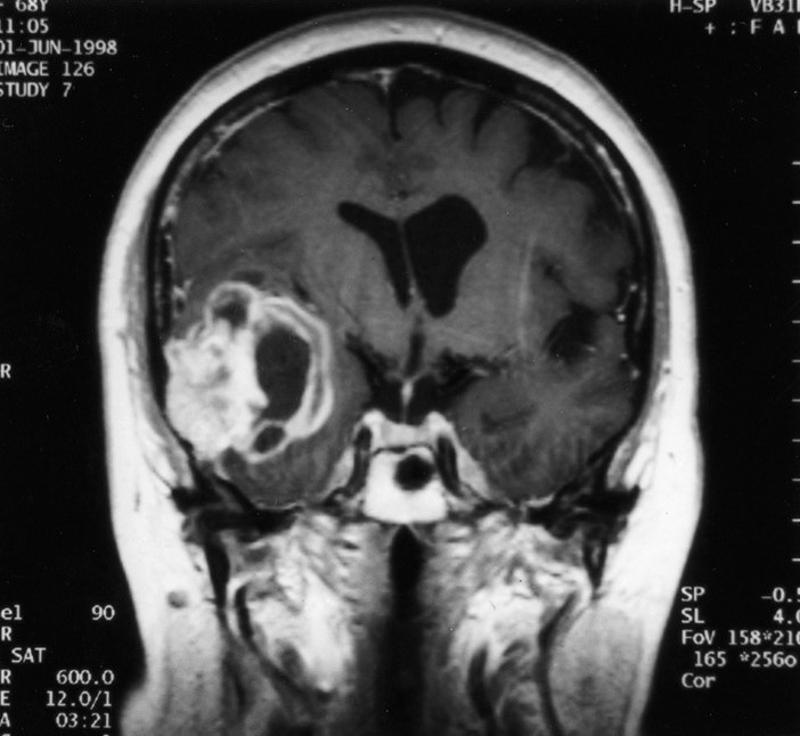

what is this aqueductal stenosis causing

hydrocephalus on MRI

what space would be more dilated: space after aqueductal stenosis or before it

before

what type of imaging is this and what is being shown

MRI: water dense in MRI

arrow poniting to periventricular damage, which is more likely with high pressure hydrocephalus